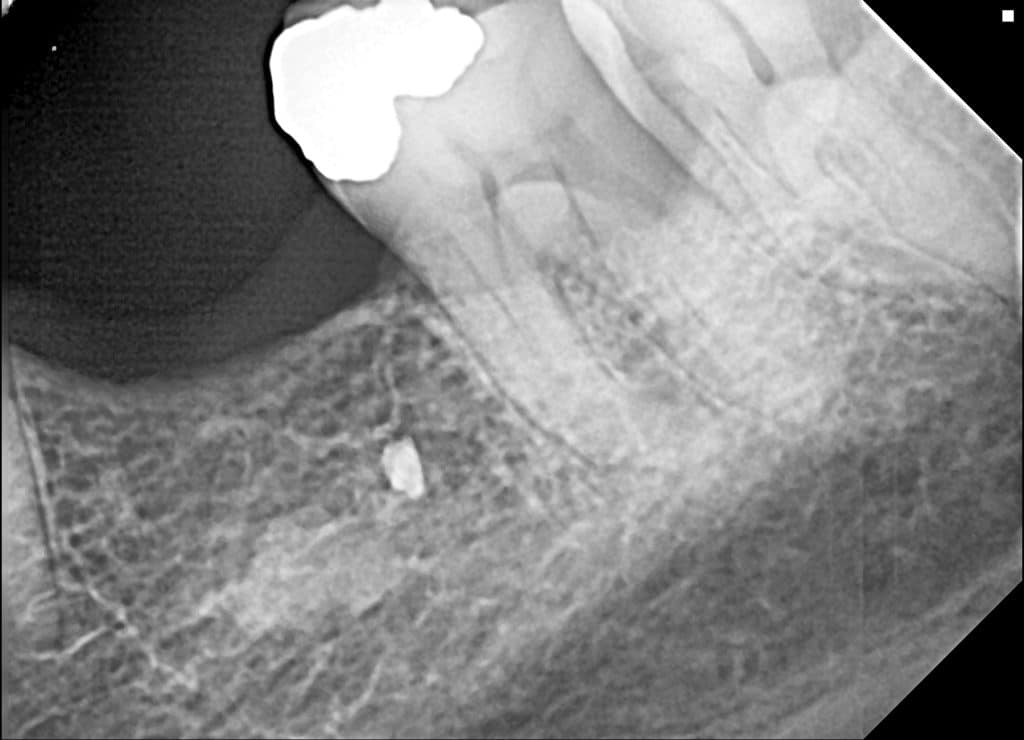

here a guided surgery case where a lower molar was replaces by an implant ,flapless ,thanks to a good digital planification and a realisation of a surgical guide